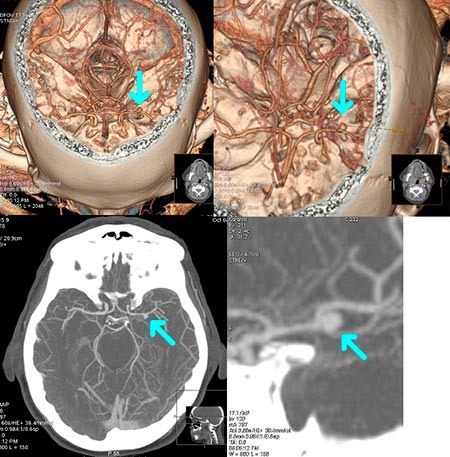

После "проката" едва заметное субарахноидальное кровоизлияние в мозге. На контрасте - аневризма средней мозговой артерии слева. Она и послужила причиной кровоизлияния.

Пример того, как может выглядеть мешотчатая аневризма средней мозговой артерии на КТ-ангиографии сосудов головного мозга